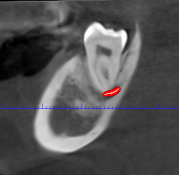

Las extracciones complejas, especialmente de terceros molares inferiores, suponen un reto quirúrgico cuando existe cercanía entre las raíces dentarias y

El CBCT (Tomografía Computarizada de Haz Cónico) es una de las herramientas diagnósticas más importantes en la odontología actual. Su

Los dientes incluidos, como caninos o muelas del juicio, son una situación frecuente en odontología. Aunque la ortopantomografía suele ser